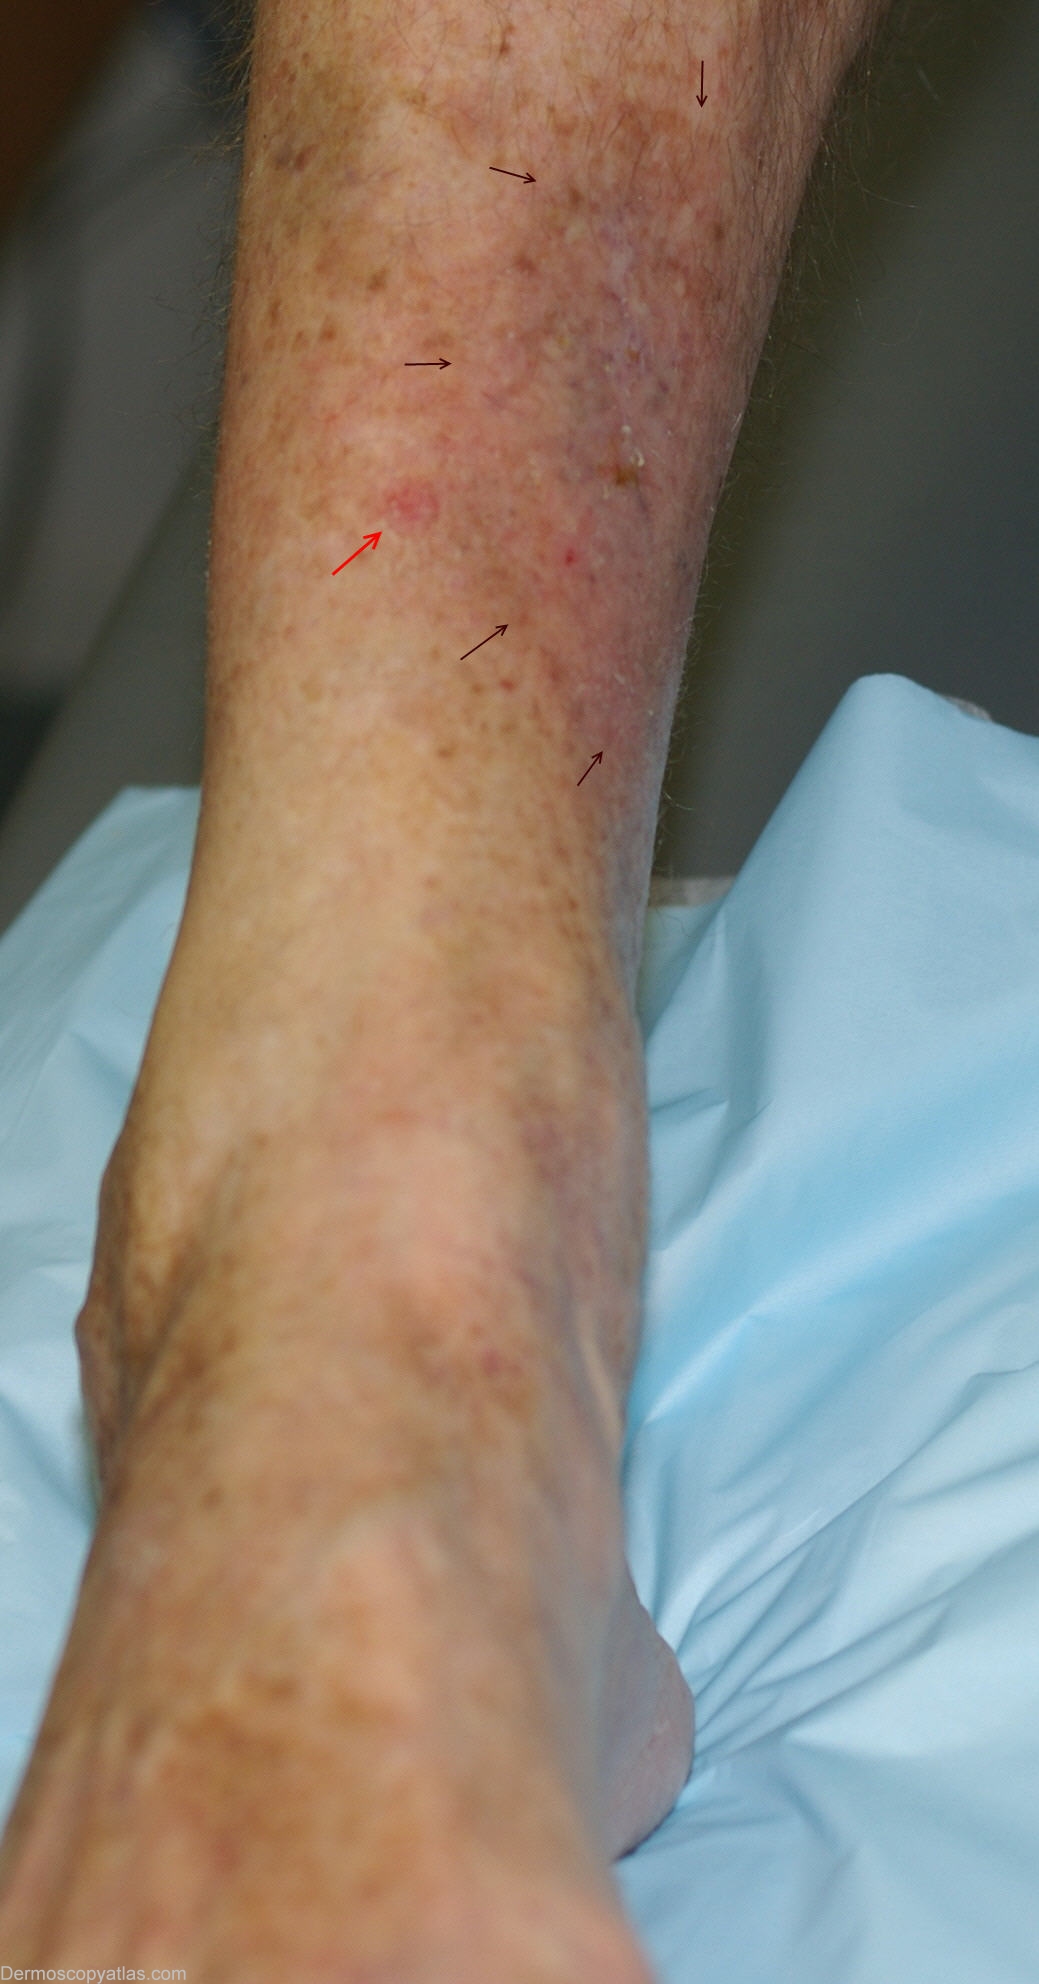

Image Number #2980 (Squamous cell carcinoma)

Site: Shins

Diagnosis: Squamous cell carcinoma

Description: Dermoscopy - Glomerular vessels with scaly surface.

History: Histopathology:    Invasive squamous cell carcinoma with Bowen's disease.